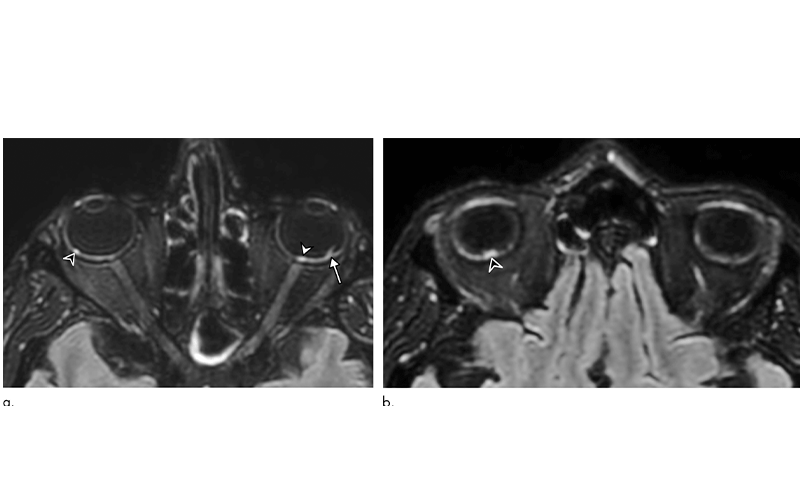

56-year-old man presenting with severe COVID-19. Diagnosis of SARS-CoV-2 infection was based on a positive quantitative real-time RT-PCR test for SARS-CoV-2 nucleic acid performed on nasopharyngeal and lower respiratory tract swabs. The patient had been hospitalized in intensive care unit for 20 days when an MRI was performed due to delayed awakening despite discontinuation of sedation. He presented with acute respiratory distress syndrome, with a median Simplified Acute Physiology Score (SAPS II) of 45. He was intubated on high-flow supplementary oxygen and placed in the prone position. A, B, 3D FLAIR-weighted MRI reformatted in the axial plane showing several hyperintense nodules of the posterior pole of the globe located in the macular region (white arrowhead) and the extramacular region (black arrowheads). Note the presence of a focal temporal retinal detachment of the left eye (arrow).